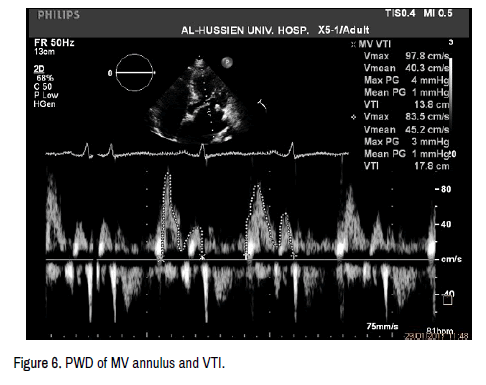

Diameter measurements are most accurate using the zoom mode with careful angulation of the transducer and with gain and processing adjusted to optimize the images. LVOT diameter is measured for subsequent calculation of the LVOT cross-sectional area (CSALVOT) to be used in the continuity equation (Figure 3). LVOT flow was recorded with pulsed wave Doppler at the same point of LVOT diameter measurement (from the apical 5-chamber view) for measuring the velocity-time integral of LV outflow (VTILVOT) (Figures 5 and 6).

cardiovascular-diseases-diagnosis-vit

Figure 6. PWD of MV annulus and VTI.

Mitral annulus diameter: From apical 4 chamber view

Diameter of mitral annulus measured at mid diastole from the medial to the lateral edges of the MV annulus. Mitral inflow (LV inflow): was recorded with pulsed wave Doppler at the same point of mitral annulus diameter measurement (from the apical 4-chamber view) for measuring the velocitytime integral of LV inflow (VTILV inflow).